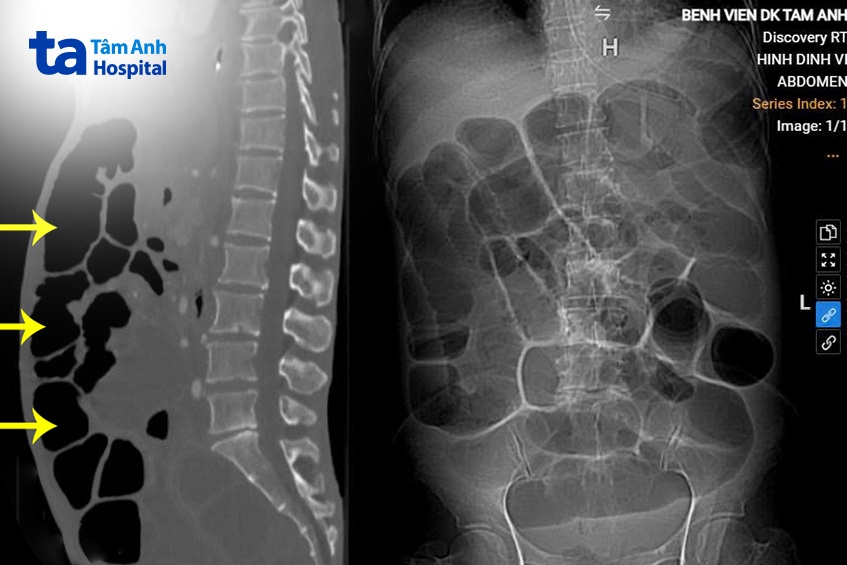

Bác sĩ Lượng chỉ định người bệnh chụp cắt lớp vi tính CT, đánh giá tình trạng ổ bụng trong ung thư dạ dày đã tiến triển, mức độ di căn xâm lấn toàn bộ đại tràng gây tắc ruột cũng như tiên lượng, đánh giá khả năng và mức độ can thiệp phẫu thuật. Kết quả cho thấy hình ảnh ruột non có thể chưa bị di căn, chít hẹp, có thể phẫu thuật giải quyết tắc ruột và để khôi phục nuôi dưỡng qua đường tiêu hóa, cải thiện thể trạng cho người bệnh để tiếp tục điều trị.

Lần lượt, bác sĩ Lượng phẫu tích các quai ruột dính vì ung thư di căn xâm lấn, mở thông hỗng tràng, đặt sonde nuôi dưỡng tiêu hóa cho bà Hằng, đưa đầu cuối hồi tràng ra da (coi như một hậu môn nhân tạo). Mặc dù ung thư di căn phúc mạc xâm lấn ruột nhưng trường hợp của bà Hằng các nhân di căn xâm lấn tắc toàn bộ từng đoạn đại trực tràng: nhân di căn xâm lấn chít hẹp toàn bộ góc hồi manh tràng, đại tràng góc lách, trực tràng, nhiều nhân rải rác mạc treo ruột non nhưng không xâm lấn chít hẹp tắc đoạn ruột non do đó còn toàn bộ ruột non sau mổ để nuôi dưỡng, đây là điều khá may mắn cho người bệnh.